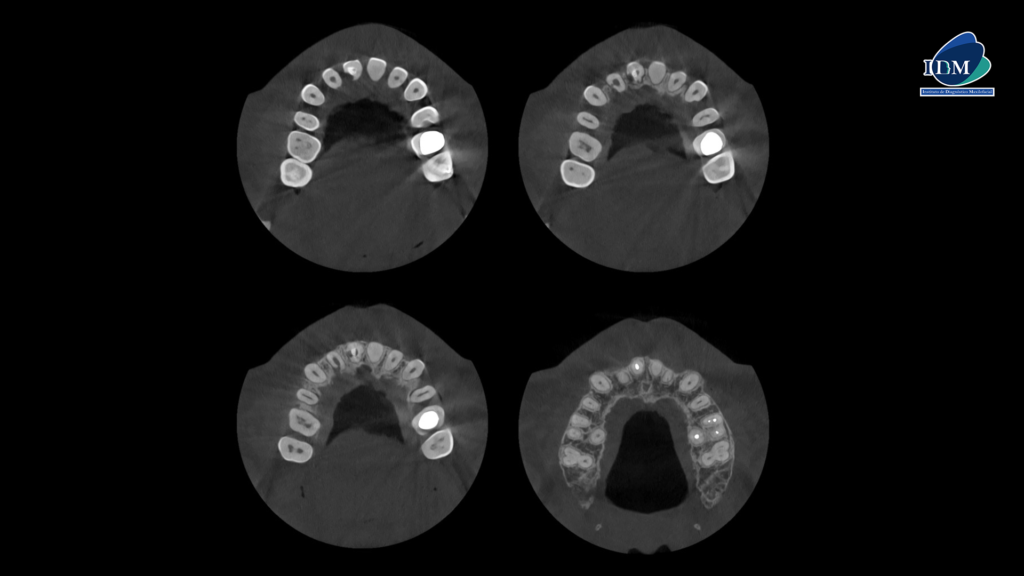

A la evaluación de la tomografía volumétrica (CBCT) en los cortes axiales (Figura 2) y transaxiales (Figura 3), se aprecia en pieza 12 obliteración del tercio apical e imagen hipodensa en pared radicular distal y palatino en tercio cervical y medio; pieza 11 tallado coronario, espigo, obturación de conducto, imagen hipodensa en pared radicular distal y palatino en tercio cervical y medio; pieza 21 obliteración de conducto radicular.

CORTES AXIALES